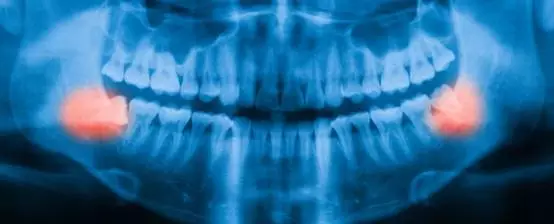

智齿拔,还是不拔,这是一个问题

要明确一点,不是所有的拔智齿都是不必要的。智齿可能会感染、引起牙齿腐烂或囊肿并损害周围牙齿,这时如果不拔掉的话会给人带来牙疼的困扰。在这种情况下,当然拔掉“第三磨牙”(智齿的学名)对患者来说最好不过。

但是除此之外,当智齿并非阻生或是阻生但未影响到健康,或甚至没有任何症状,研究人员开始怀疑在这些情况下拔除智齿的必要性。